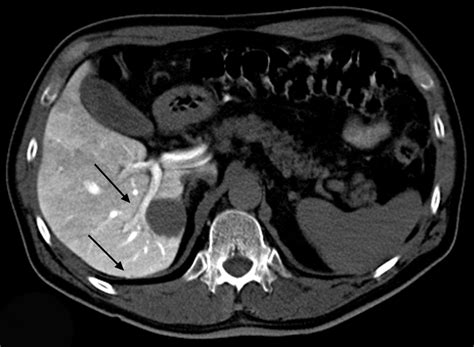

In the CTAP procedure, a pigtail catheter is inserted into an artery, typically in the leg, and guided to the area of interest using fluoroscopy. Once in place, a contrast agent is injected through the catheter, which highlights the blood vessels and allows them to be visualized on the CT scans. The resulting images provide valuable information about the structure and function of the blood vessels, which can be used to diagnose and treat a range of vascular conditions, including aneurysms, arteriovenous malformations, and vascular stenosis.

- A contrast agent is injected through the catheter to highlight the blood vessels and allow them to be visualized on the CT scans.

4. CT scanning: The patient is then placed in the CT scanner, which takes detailed images of the blood vessels and surrounding tissues.

5. Image interpretation: The resulting images are interpreted by a radiologist, who looks for any signs of vascular disease or other conditions that may require treatment.